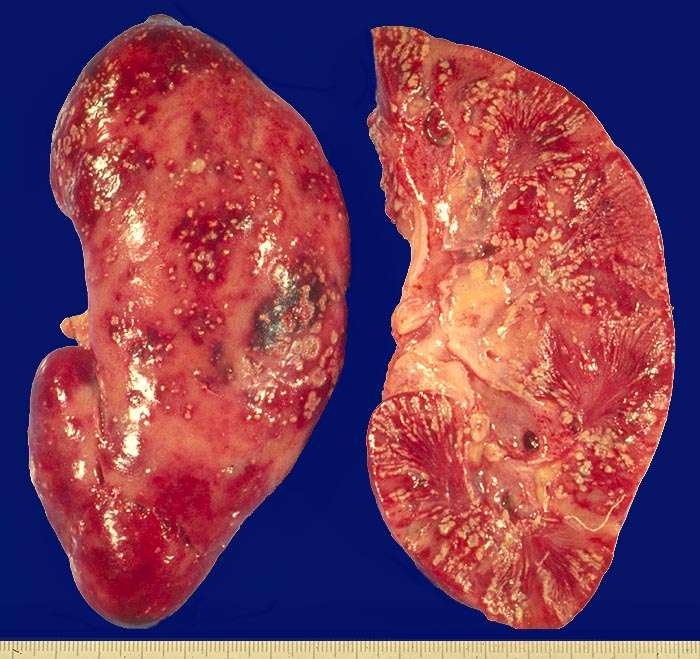

Akute Pyelonephritis

Schwerste akute Pyelonephritis. Die Nierenoberfläche zeigt eine fleckförmige Hyperämie. In den hyperämischen Herden multiple, unterschiedlich grosse, rundliche, gelbe Eiterherde. Auf der Schnittfläche sind Eiterstrassen von der äusseren Nierenrinde bis zur Papillenspitze erkennbar.